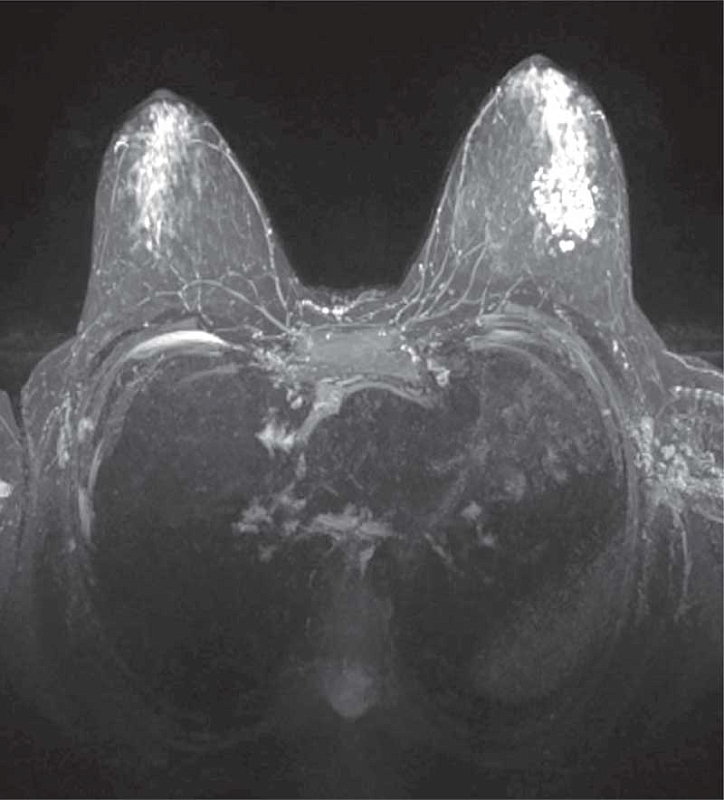

Рис. 7. МРТ с контрастным усилением: фиброзно-кистозная мастопатия у 17-летней пациентки

УЗИ показывает расширение протоков, утолщение связок Купера, мелкозернистую гетерогенность железистой ткани, возможные анэхогенные кисты, ЦДК – тенденцию к гиповаскуляризации. При узловом варианте очаги пониженной эхогенности без четкого ободка, с элементами локального фиброза [6, 7, 16] (рис. 6).

При неоднозначной эхографии, отсутствии адекватной визуализации при УЗИ показано выполнение магнитно-резонансной томографии (МРТ) с контрастированием (рис. 7).